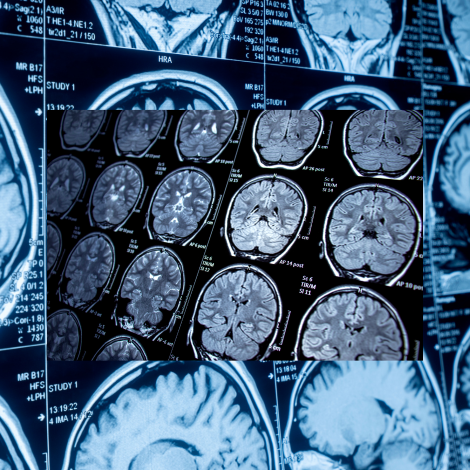

• BRAIN MRI

MRI of the brain can help to diagnose: Tumors and cysts, aneurysms, disorders of the eyes and the inner ear, stroke, diseases of the pituitary gland, neurological disorders such as multiple sclerosis, evaluate traumatic brain injury, causes of headache, giddiness, vertigo, dementia or memory loss, seizures etc and any issues with brain development.